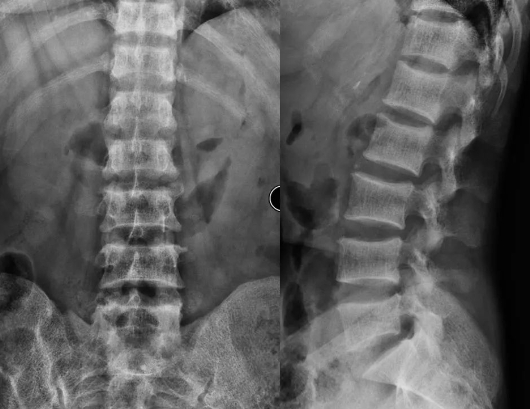

基于MRI的腰椎间盘突出物体积的计算!